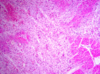

The most typical morphological complications

of this lesion are:

name 4

rupture/aneurysm

pericarditis

mural thrombus

emboli